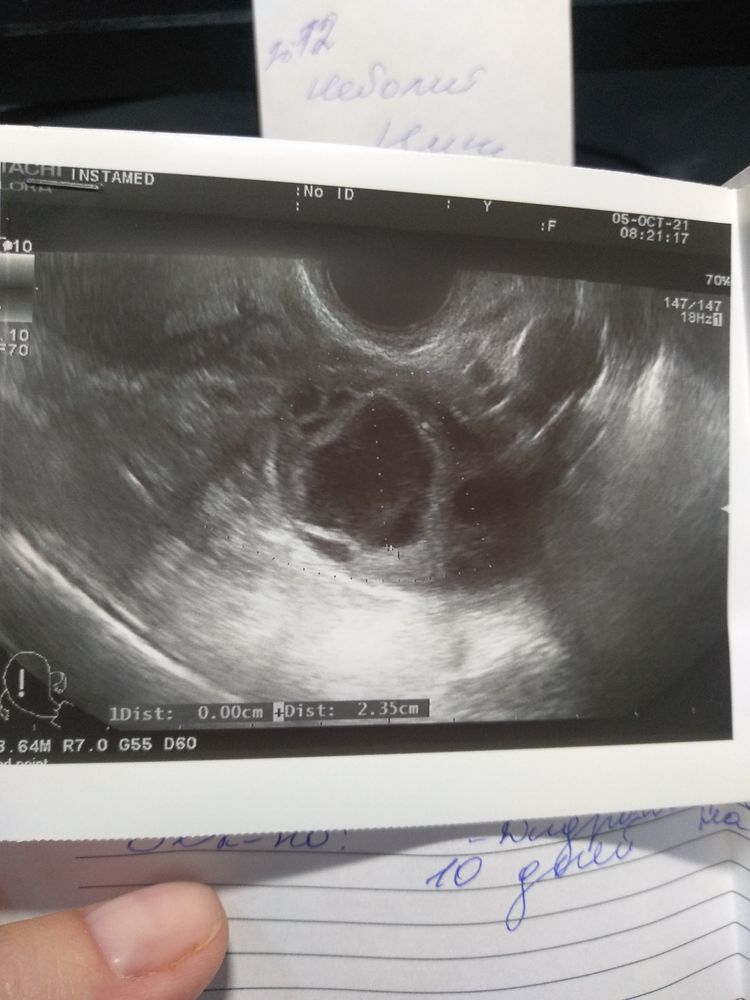

Девочки, подскажите это жёлтое тело или киста? Гинеколог сказала ЖТ, но смущают размеры 23,5 мм

У меня жт до 24 бывало,говорили,что это просто отлично

Нормальные размеры. У меня двухсторонние кисты жт, 32 и 35мм